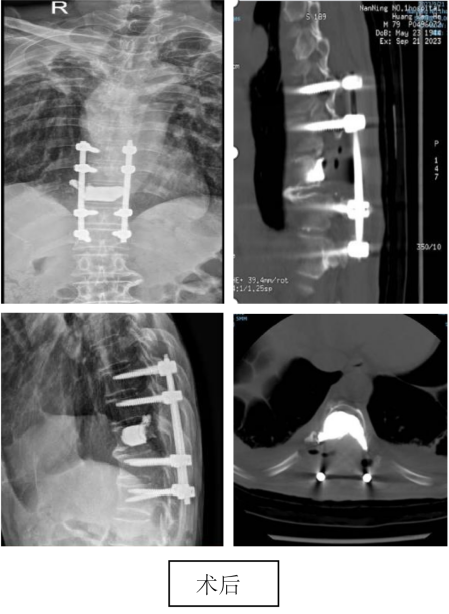

图注:上胸椎巨大肿瘤,联合心胸外科行肿瘤切除术,术后患者下肢肌力由术前2级恢复到4级。